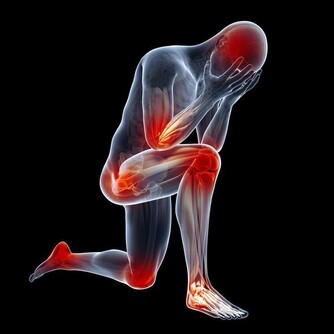

降血壓藥物、安息藥:坐位服藥後躺臥

有些藥物,如哌唑嗪、特拉唑嗪等用於降血壓時,在首次給藥或加大劑量時,應坐位服藥後立即躺臥。服用起效快的安息藥(如咪達唑侖、唑吡坦等),應在臨睡時坐位服藥後躺下,以免產生摔倒意外。

姿態不對的傷害:易產生直立性低血壓或摔倒。